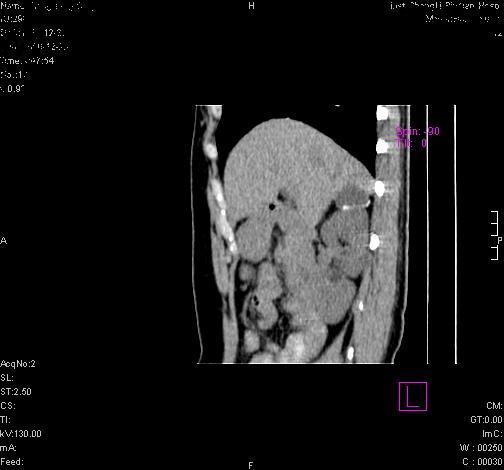

标题: CL0340:【】肾上腺囊肿,比较典型。

患者为年轻女性,查体发现右侧肾上腺囊性占位。无临床体征。

这么漂亮的图像,一看一目了然。典型的右侧肾上腺囊肿,周围有钙化。感谢搂主!

最好做个增强,进一步明确为佳

漂亮!最好做个增强及上传ct值,进一步明确为佳 。